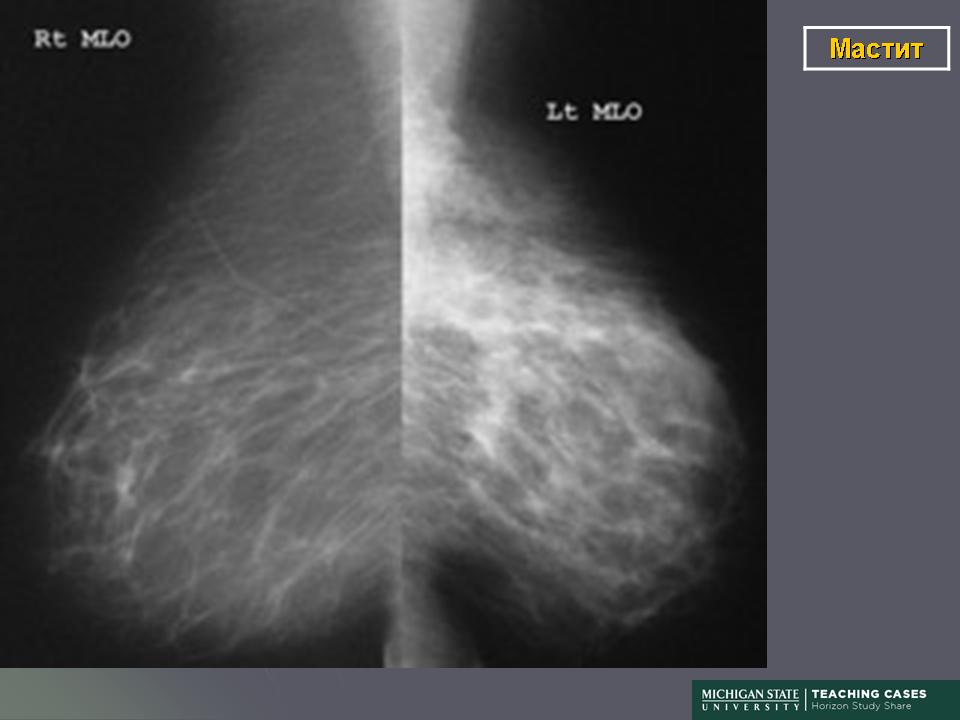

Гранулематозный мастит